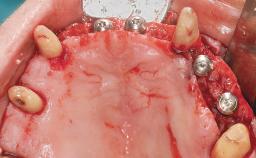

Conventional Loading of Eight Implants in the Maxilla and Final Restoration with a Full-Arch Gold-Ceramic FDP

A 35-year-old Caucasian female presenting with advanced periodontal disease involving both the maxillary and the mandibular dentition was referred for evaluation. The patient, a non-smoker in good general health, requested treatment for recurrent periodontal abscesses, tooth mobility, and discomfort during chewing, as well as restoration of her missing teeth with a fixed prosthesis to improve mastication and esthetics. All residual maxillary teeth exhibited plaque deposits, deep pockets, bleeding on probing, and class III mobility and were evaluated as hopeless. All residual mandibular teeth except tooth 37 could be maintained after periodontal therapy.

# of Implants 8

Bone Augmentation Horizontal|Staged|Vertical

Augmentation Materials Autogenous block(s)

Soft Tissue Grafting Staged

Defining Characteristics Fully edentulous upper jaw to be rehabilitated with four or more implants